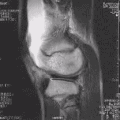

МРТ коленного сустава.